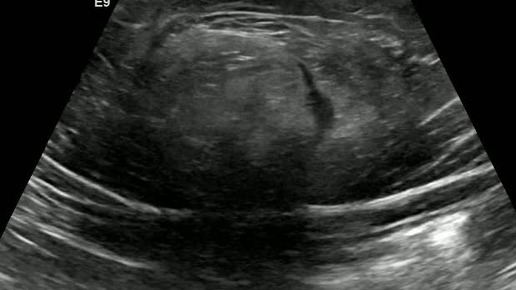

Видео к статье "Ущемленная грыжа белой линии" https://dzen.ru/a/Z4dbuDYQdUQl35Wp

Ультразвуковые находки от врача УЗД Зорина Я.П.